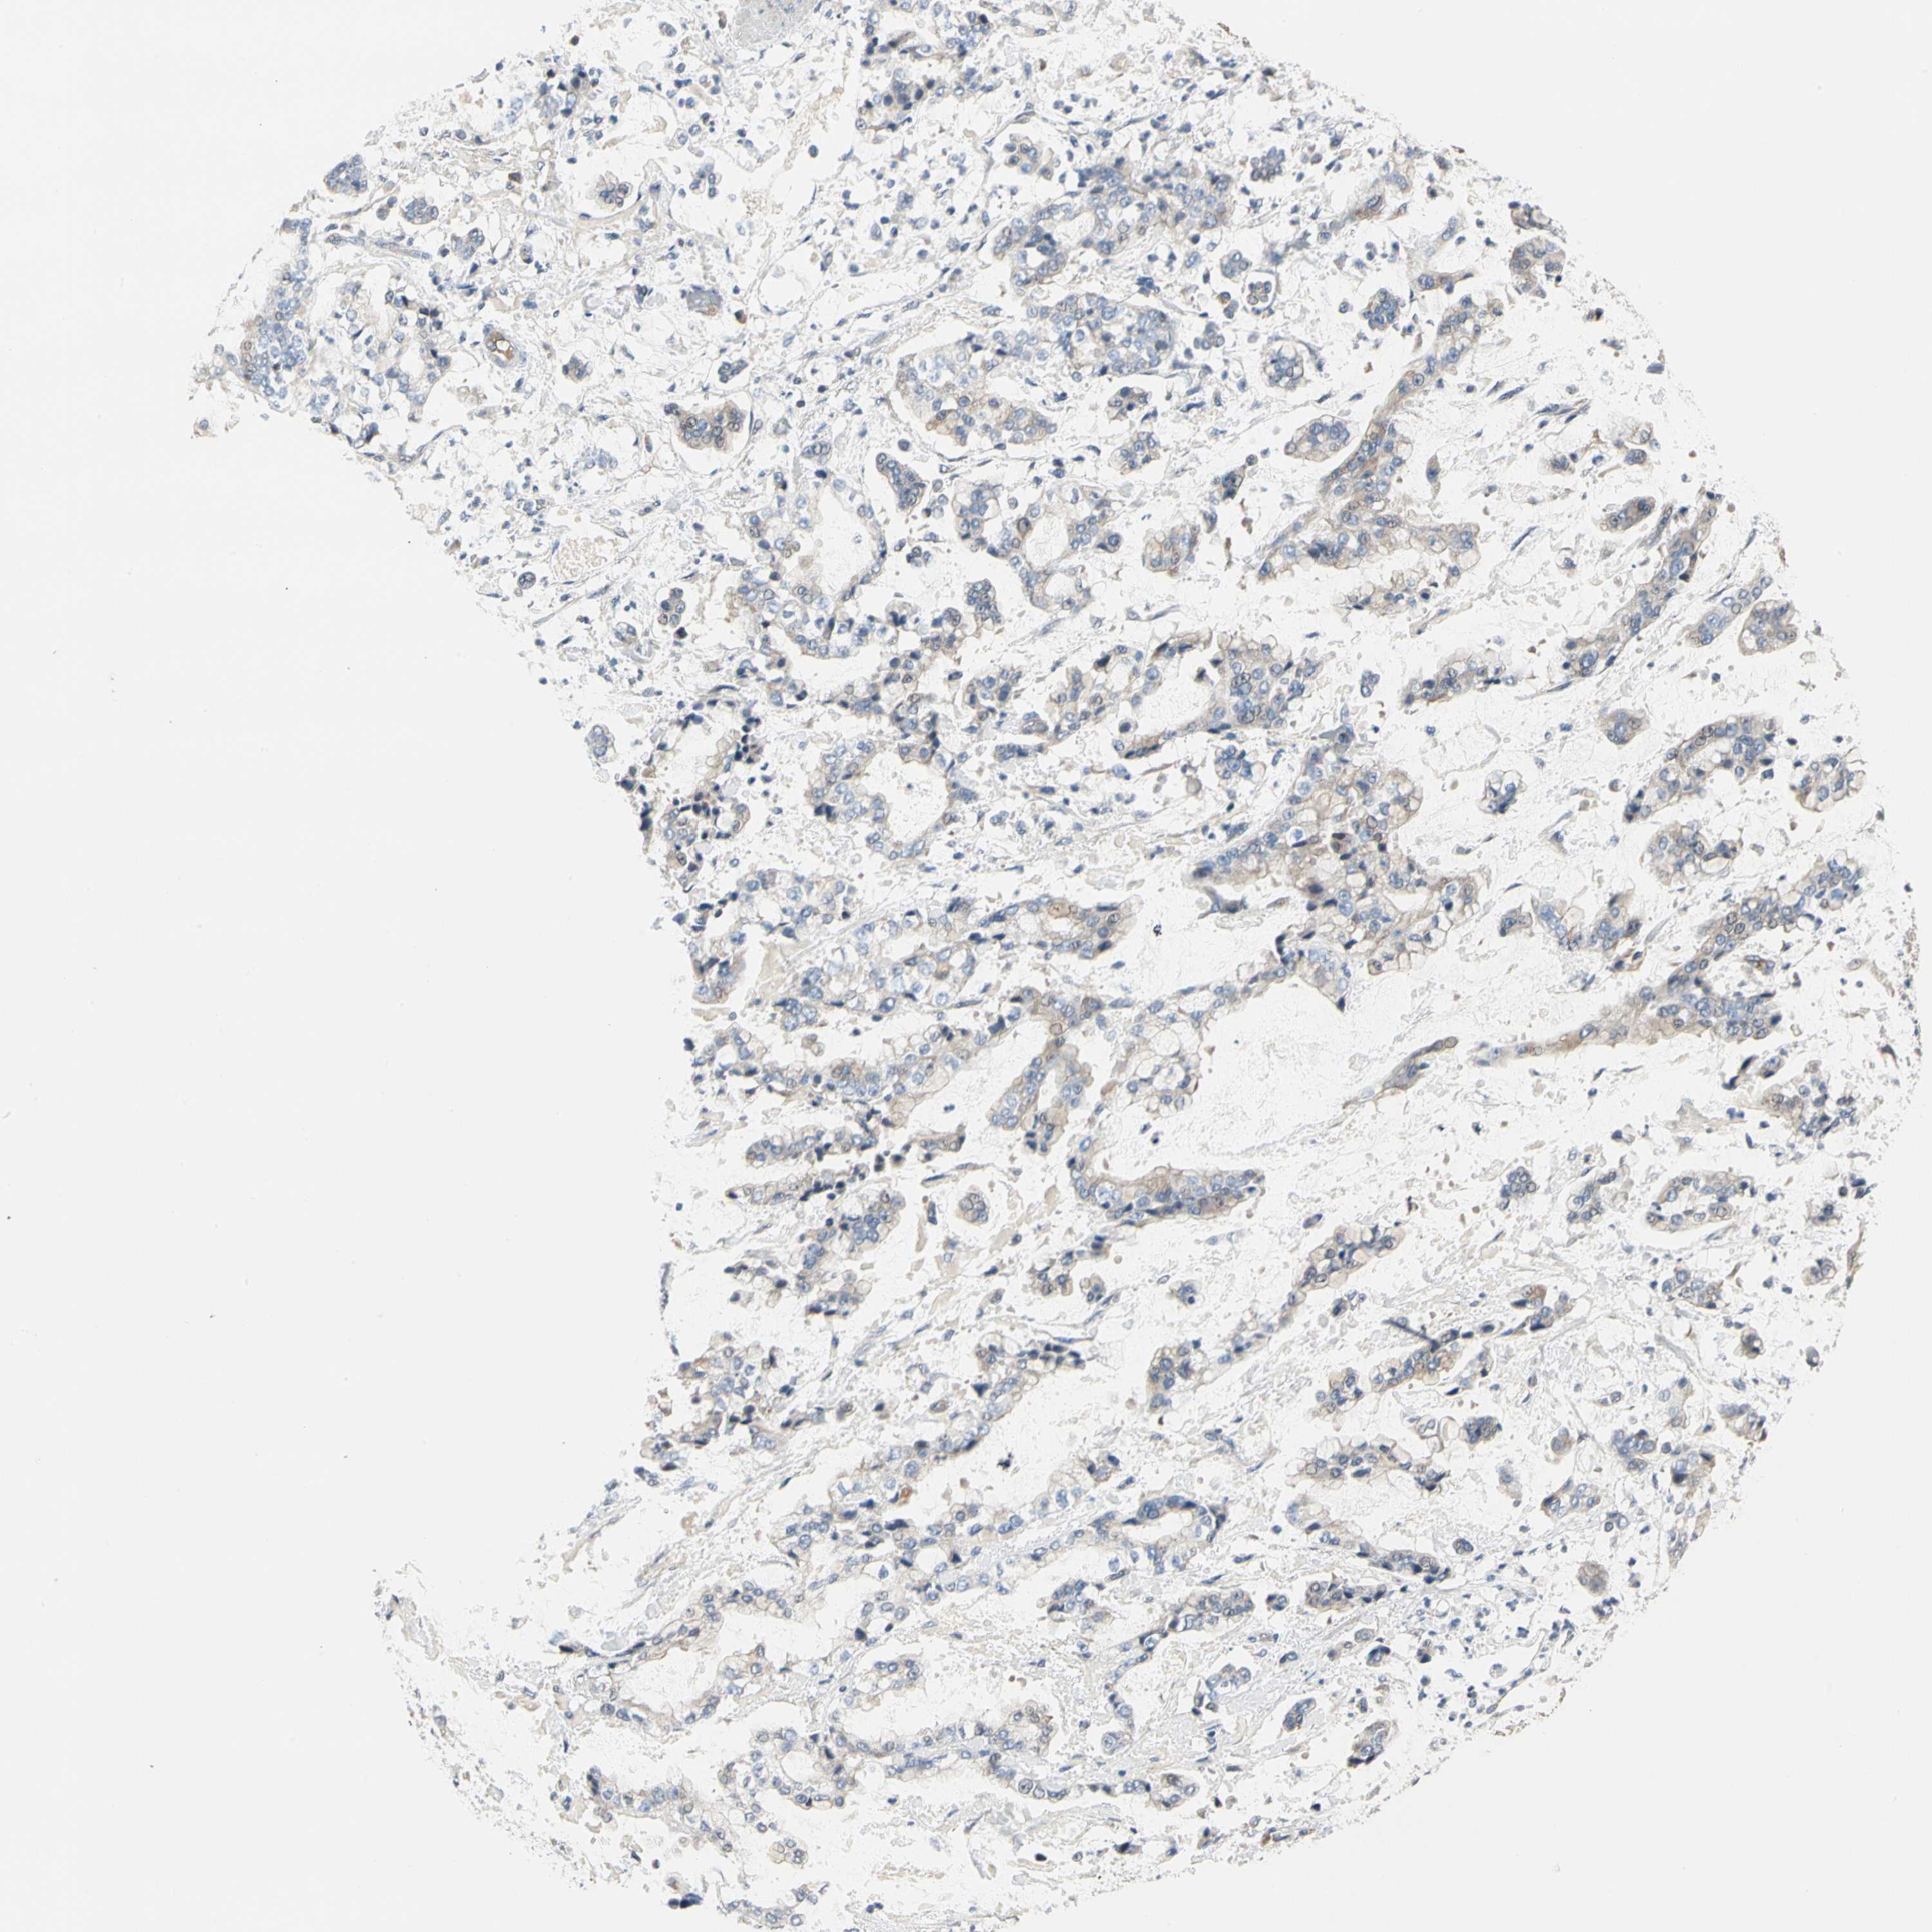

STOMACH CANCER - Protein expressioni

A mouse-over function shows sample information and annotation data. Click on an image to view it in a full screen mode. Samples can be filtered based on level of antibody staining by selecting one or several of the following categories: high, medium, low and not detected. The assay and annotation is described here.

Antibody stainingi

Antibody staining in the annotated cell types in the current human tissue is reported as not detected, low, medium, or high, based on conventional immunohistochemistry profiling in selected tissues. This score is based on the combination of the staining intensity and fraction of stained cells.

Each image is clickable and will lead to virtual microscopy that enables deeper exploration of all samples and also displays staining intensity scores, fraction scores and subcellular localization as well as patient and tissue information for each sample.

Antibody HPA007159

Staining

High

Medium

Low

Not detected

Intensity

Strong

Moderate

Weak

Negative

Quantity

>75%

75%-25%

<25%

None

Location

Nuclear

Cytoplasmic/membranous

Cytoplasmic/membranous,nuclear

Adenocarcinoma, NOS